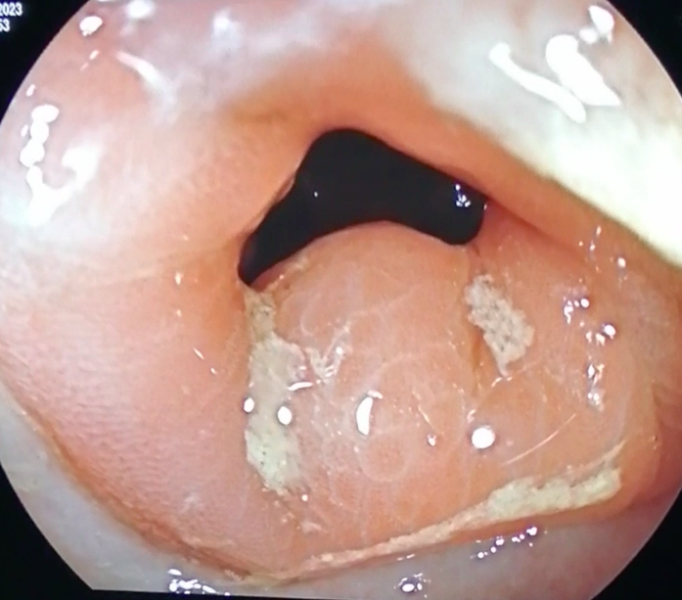

From ring to ring on the road to the eosinophilic abyss - a doubly complicated presentation of Eosinophilic oesophagitis!

Fotografia